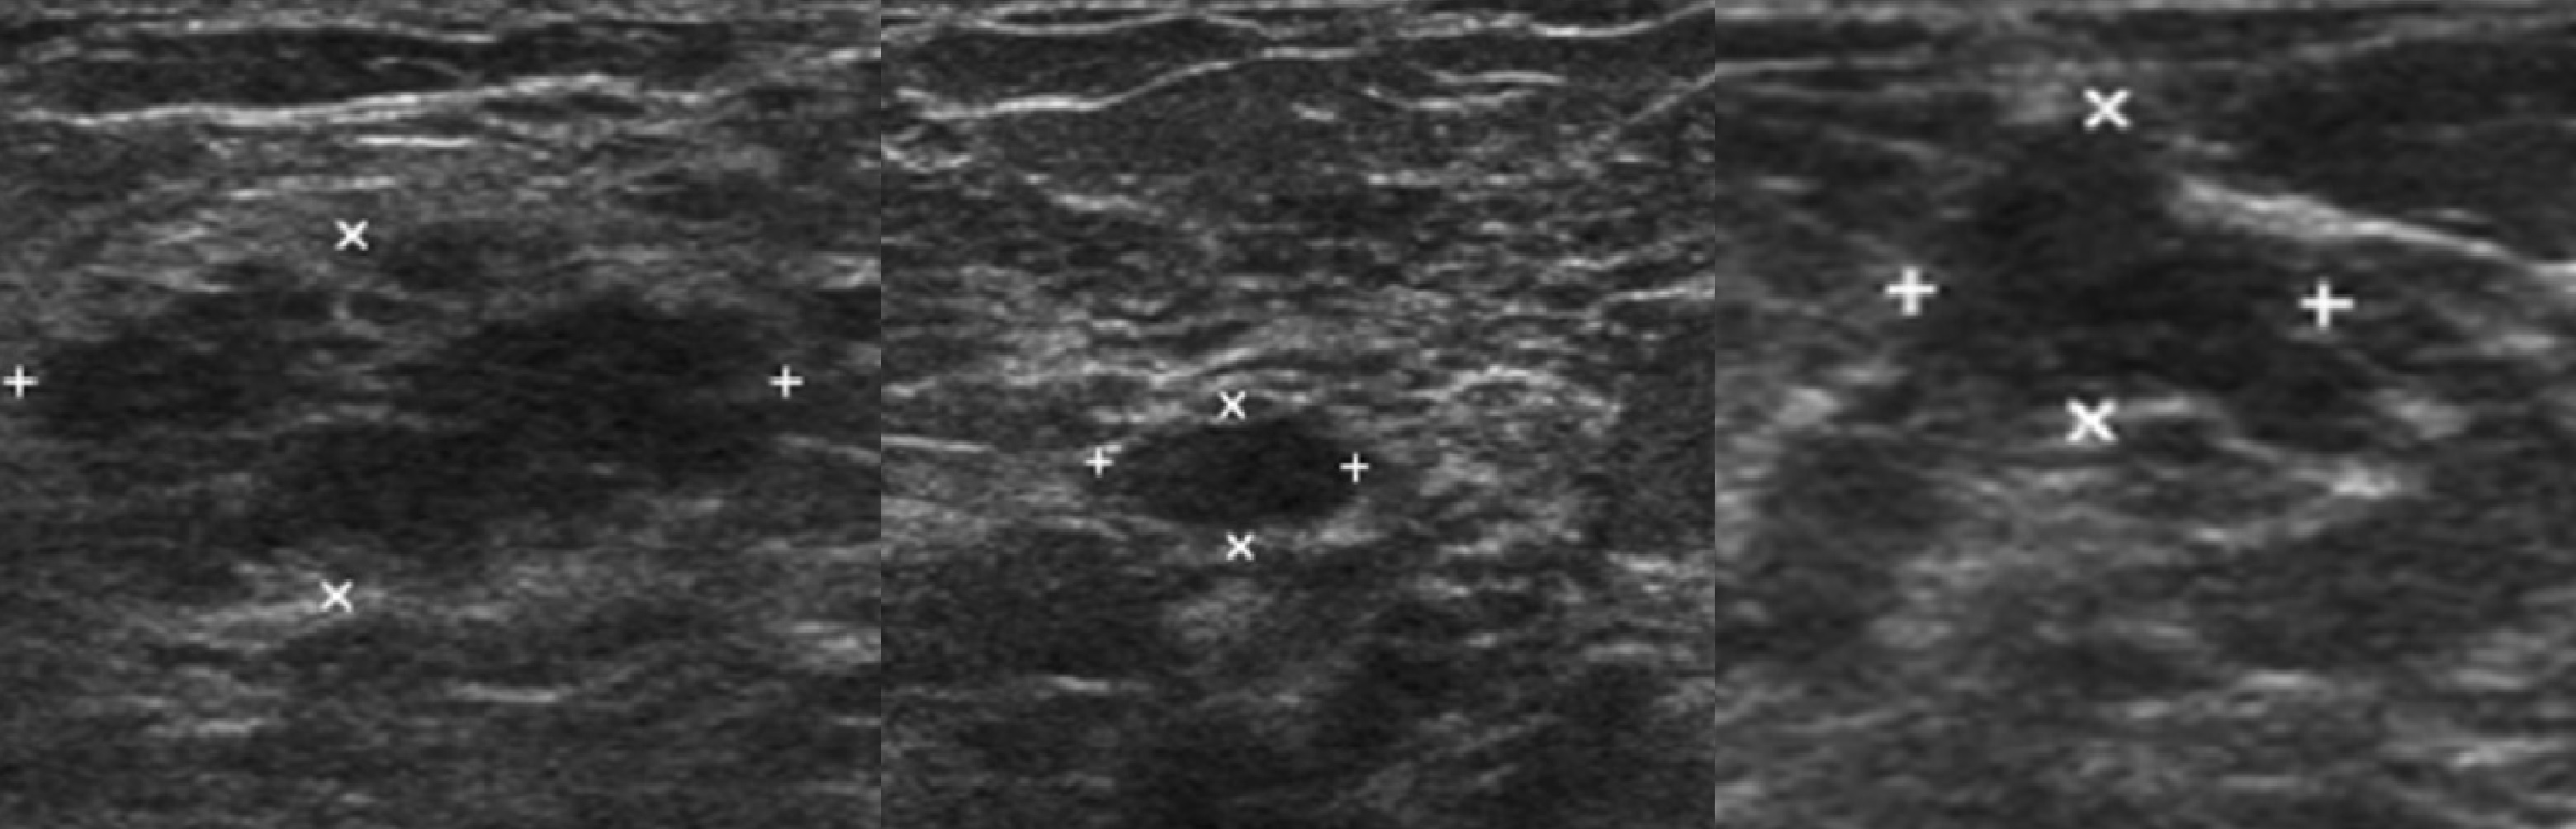

УЗИ молочных желез — информативный и безопасный метод диагностики, с помощью которого можно точно оценить состояние желез, обнаружить доброкачественные и злокачественные образования, уточнить диагноз. Это доступное по цене исследование безвредно и не несет лучевой нагрузки. Оно имеет большое значение в ранней диагностике заболеваний и нередко применяется в профилактических целях. На УЗИ может направить маммолог, онколог, эндокринолог, гинеколог.

Пациентка раздевается до пояса и ложится на кушетку, заводит руку за голову. Врач наносит на кожу груди специальный гель для улучшения проводимости ультразвуковых волн и облегчения скольжения, после чего приступает к обследованию — водит по коже датчиком. Затем процедуру повторяют со второй молочной железой. На мониторе аппарата выводится изображение тканей органа. Процедура безболезненна, занимает не более 20–25 минут.

Сделать УЗИ молочных желез можно в качестве первичной диагностики и для уточнения уже предполагаемого диагноза. Метод основывается на способности высокочастотных ультразвуковых волн с различной скоростью отражаться от тканей с разной плотностью.

Под контролем УЗИ специалист может взять пункцию из подозрительных новообразований для дальнейшего изучения материала в лаборатории. Это позволяет обеспечить точность манипуляций и повышает безопасность инвазивных методов.

Поставить диагноз мастит может только врач-маммолог при осмотре и после подтверждающих результатов лабораторных исследований и УЗИ молочных желез.

Диагностировать липому может врач хирург после визуального осмотра и пальпации места новообразования. По рекомендации врача может потребоваться УЗИ мягких тканей, маммография или биопсия с цитологическим или гистологическим исследованием.

- ультразвуковое исследование